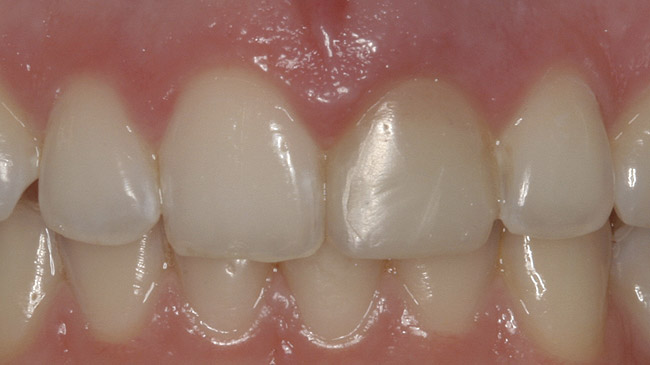

After the zirconia abutments were torqued to 20 Ncm, cotton and composite were used to cover the screw access openings. Figure 7 and Figure 8 show the finished feldspathic porcelain crowns on implants in sites Nos. 24 through 26, and on teeth Nos. 22, 23, 27, and 28; all crowns were cemented with dual-cure resin cement. Good remodeling of gingival architecture is also apparent in Figure 7. As predicted, the free gingival margin (FGM) on No. 23 is approximately 2 mm coronal to those of the adjacent implant crowns on Nos. 24 through 26 (Figure 7); as per the patient’s initial statement, this discrepancy was not an esthetic concern to her. Figure 9 shows the final post-restoration periapical view.

This patient faced a unique situation, perhaps not previously reported: retaining a healthy mandibular lateral incisor knowing this would create an esthetic compromise. Indeed, while the discrepancy in gingival-margin height is noticeable in retracted view (Figure 7), it does not show in full smile (Figure 8).

Figure 7  Finished feldspathic crowns, teeth Nos. 22, 23, 27, 28, and implant sites 24 through 26 showing good gingival emergence profile—post-cementation facial view.

Figure 7

Figure 8  Full smile—finished feldspathic crowns on teeth Nos. 22, 23, 27, and 28; implant crowns in sites 24 through 26; esthetic harmonization with opposing dentition.

Figure 8